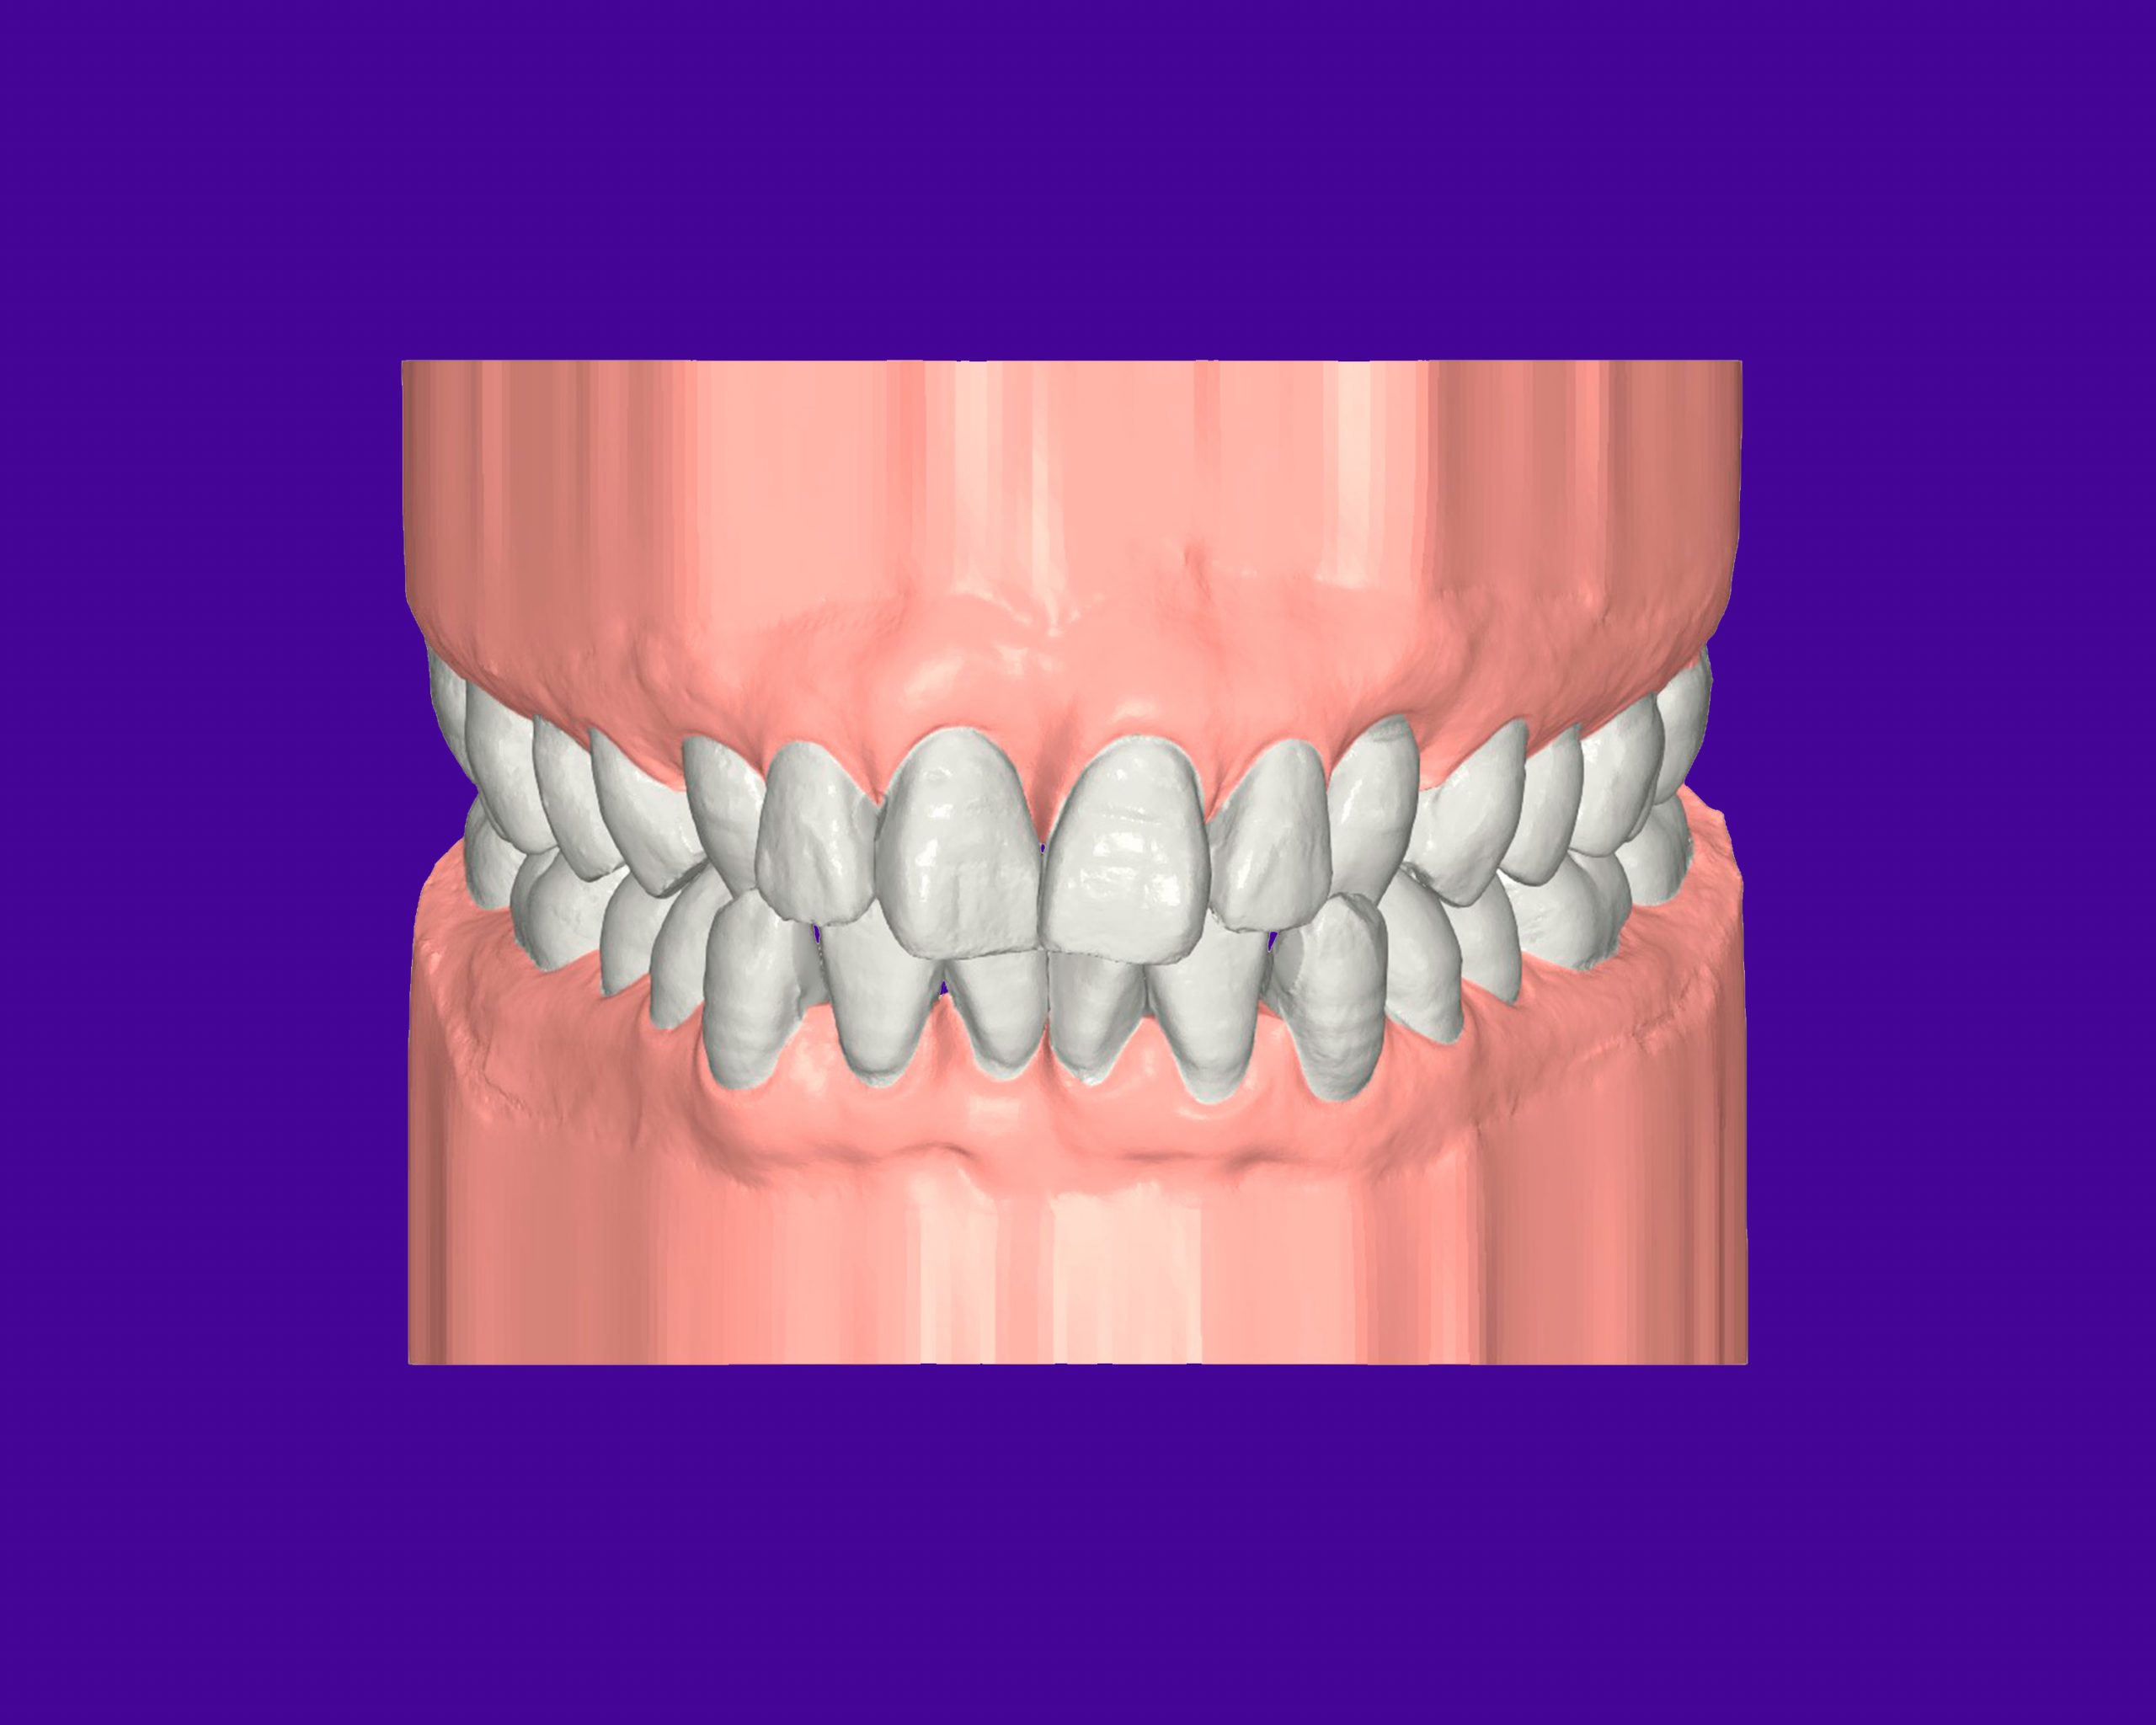

Maloclusión

Se caracteriza por una alineación incorrecta de los dientes, donde los dientes superiores e inferiores están en una relación normal, pero hay una falta de espacio que provoca que los dientes se solapen o estén apiñados.

Este problema puede generar dificultad para mantener una correcta higiene dental y afectar la estética de la sonrisa